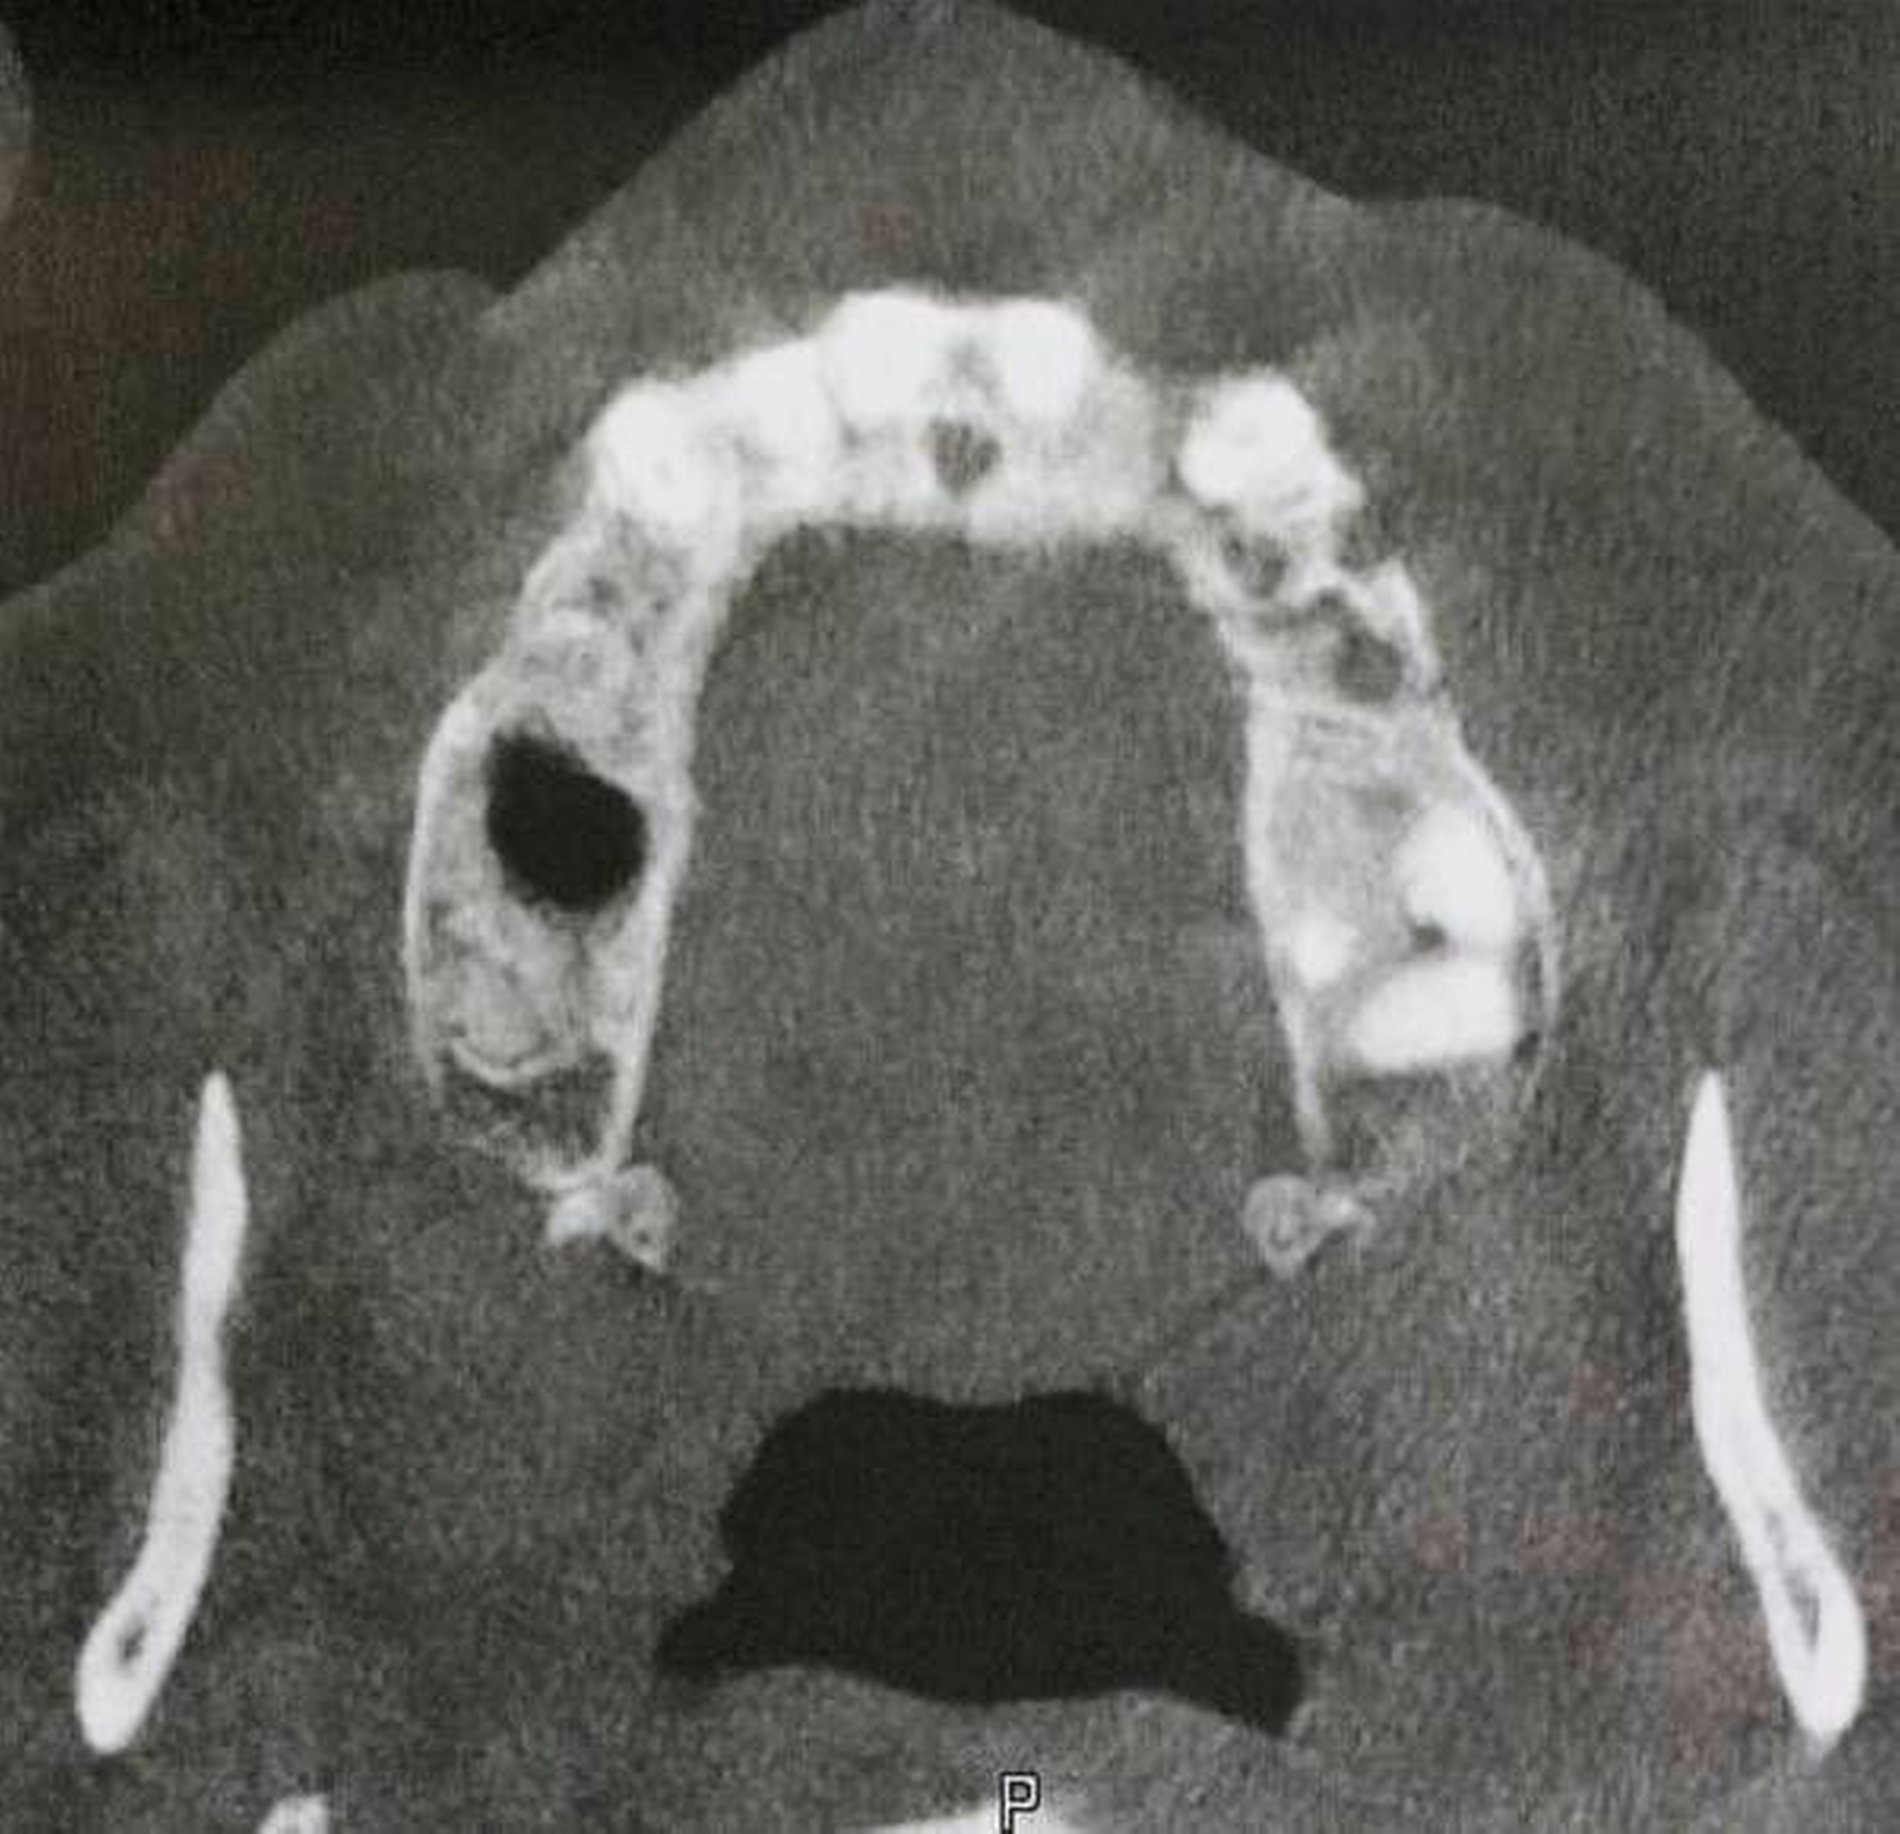

Die Mundschleimhaut in diesem Bereich war gerötet und atrophisch verändert, auf Palpation war Sekret exprimierbar, ein Abstrich wurde genommen. Bläschen oder Krusten waren nicht eruierbar. Der Zahn 23 war in seiner Alveole beweglich und wurde nur über die bestehende Brückenkonstruktion regio 21 bis 23 gehalten. An den Zähnen 23, 27 und 28 fanden sich jeweils erhöhte Taschensondierungstiefen von 9 bis 10mm. In der radiologischen Bildgebung (fremd-OPG / DVT) zeigte sich ein osteolytisch veränderter Knochen mit Sequesterbildung regio 23 bis 026 (Abbildung 3). Die angrenzende Kieferhöhlenschleimhaut war polypös verändert.